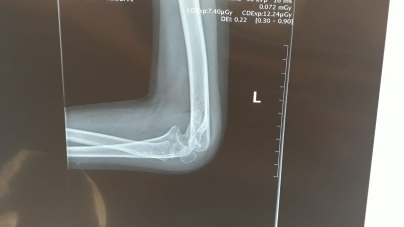

Situație dificilă pentru o familie din satul Ocoliș, comuna Groși. Băiatul în vârstă de numai…